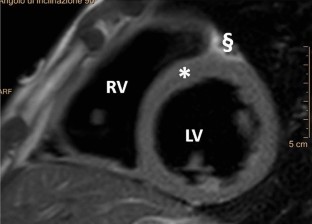

Fig. 1